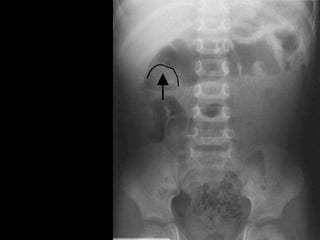

Plain x-ray abdomen

• May be normal.

• Meniscus sign:

• Crescent of gas within colonic lumen that

outlines the apex of intussusceptum.

• Little air in small intestine.

Meniscus

sign

Plain x-ray abdomen • May be normal. • Meniscus sign: • Crescent of gas within colonic lumen that outlines the apex of intussusceptum. • Little air in small intestine.